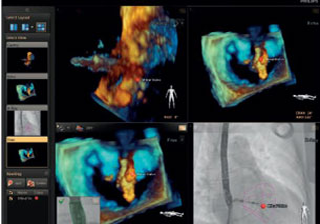

بعد تشخيص مريض بارتجاع الصمام الميترالي، ما هي خيارات العلاج المتوفرة له؟ إذا لم يكن مرشحًا للخضوع لعملية القلب المفتوح، يمكنك التفكير في معالجته عبر إصلاح الصمام الميترالي باستخدام القسطرة (TMVR). وفي يومنا الحالي، تؤمن حلول التصوير المبتكرة والأجهزة المتوفرة حديثًا خيارات جديدة لبعض المرضى.

التخطيط للإجراءات باستخدام البيانات الكمية الموثوقة.

متابعة إجراءات التدخل وتقييمها من خلال الاتصالات الموسّعة بين أعضاء فرق طب القلب.